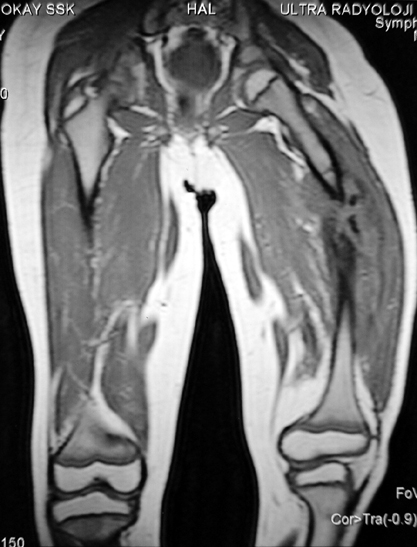

Femur Osteomyelit

Kronik osteomiyelit, kemik ve yumuşak dokularda nekroza yol açar. Ölü kemik, patojen mikroorganizmalara ev sahipliği yapan bir nidus oluşturur. Konağın savunma sistemleri, mikroorganizmalarla baş etmek için sıklıkla optimal koşullarda değildir. Dolaşım bozukluğu yüzünden enfeksiyon bölgesine antibiyotikler yeterince ulaşamaz. Bu nedenle ölü dokuların ortamdan tamamen uzaklaştırılması gerekir (radikal debridman).

Uygun radikal debridman tüm nekrotik kemik ve yumuşak dokuların çıkartılmasını gerektirir, ve sıklıkla uzuvda instabiliteye neden olur. Kalan kemik ve yumuşak doku defektinin bir şekilde fiksasyonu ve rekonstrüksiyonu gereklidir. İlizarov’un ortaya koyduğu distraksiyon osteogenezi yöntemi, kaynamanın elde edilmesi, deformitenin düzeltilmesi, bacak boy eşitsizliğinin giderilmesi ve segmental defektlerin rekonstrükte edilmesi için başarıyla kullanılmaktadır.